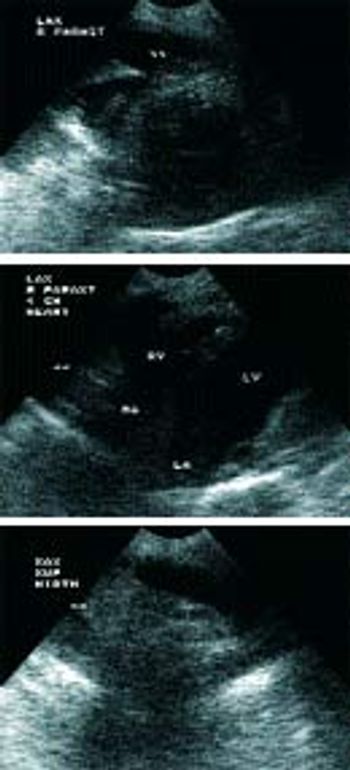

Q. Could you provide a brief review of car Could you provide a brief review of cardiomyopathies in cats?

Q. Could you provide a brief review of mitral valve insufficiency in older dogs?